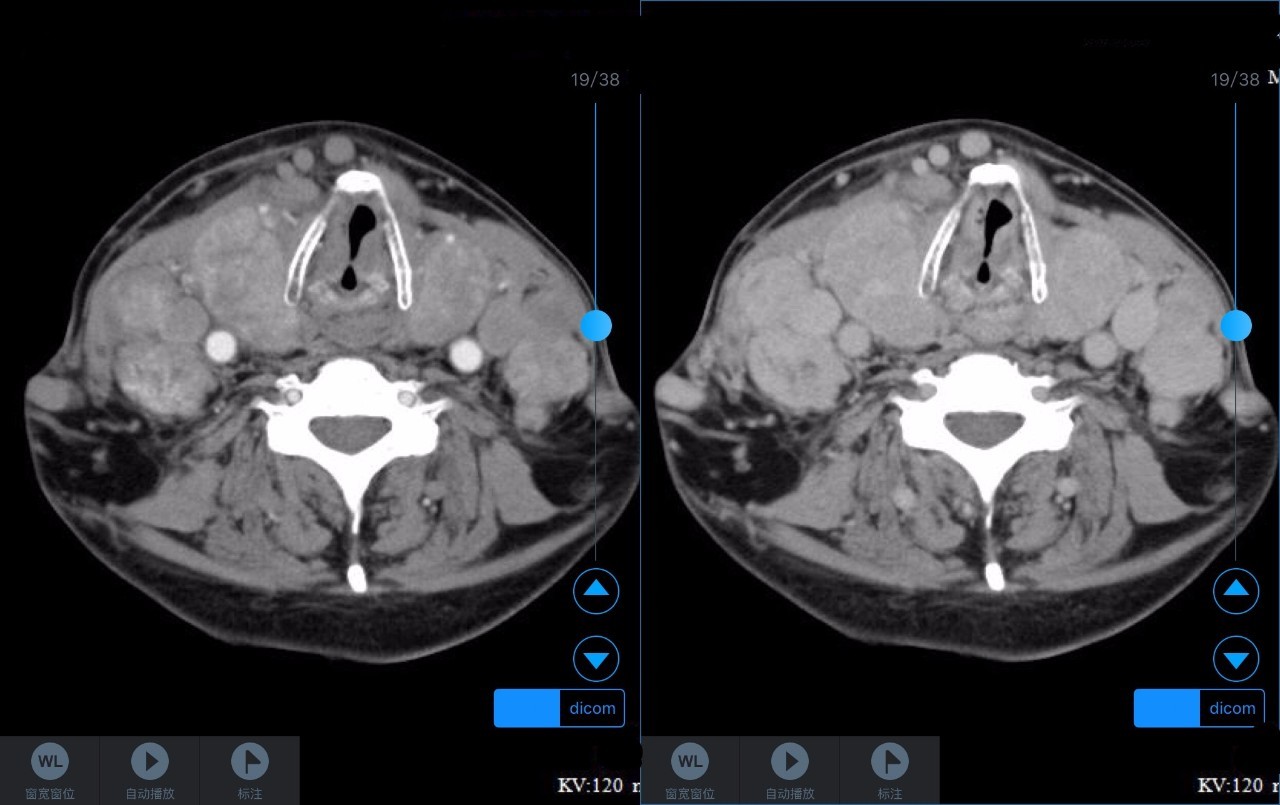

▼患者CT平扫(右)及增强CT(左)检查报告资料

Z主任 甲状腺肿大,内见弥漫多发结节,界限不清,甲状腺包膜毛糙。双侧颈部、锁骨上、纵隔多发肿大淋巴结,病变均强化明显,密度不均,边缘毛糙,考虑甲状腺恶性肿瘤伴多发淋巴结转移,或甲状腺内也是转移瘤。Castleman病多灶者少见,一般病变边缘光整,也不会累及甲状腺。建议穿刺活检。 C主任 双侧甲状腺肿大,密度不均,不均匀强化,甲状软骨未见明显骨质破坏气管右侧壁受压;双侧颈部多发肿大淋巴结,不均匀强化;考虑为甲状腺恶性占位性病变伴双侧颈部淋巴结转移,建议组织学进一步检查。 声明:以上资料均来自和缓名医平台的真实案例,为保护用户隐私,均用化名代替。资深医师Z咨询反馈